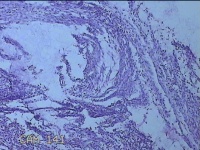

左卵巢囊肿

性别

女

年龄

32岁

临床诊断

左卵巢巧克力囊肿破裂

一般病史

下腹疼痛2天,加重10小时。

标本名称

大体所见

灰白暗红色囊壁样组织5.3x2x1.3cm一堆,表面糜烂,因已切开,囊内容物已流失,囊壁厚0.1cm。

图1